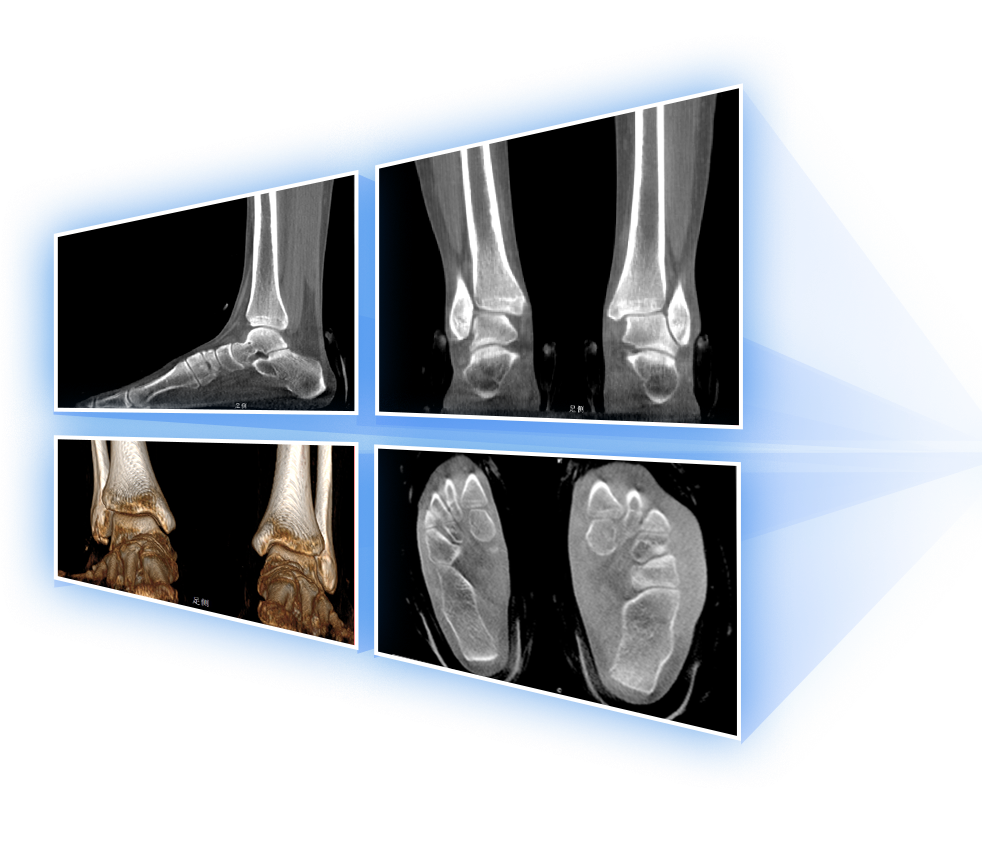

足踝

精準(zhǔn)診斷

手術(shù)方案規(guī)劃

術(shù)后隨訪(fǎng)

VR體繪制重建